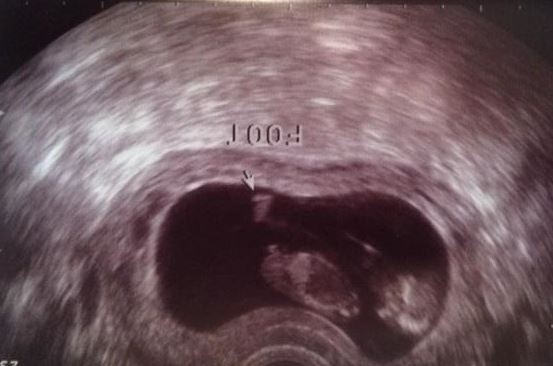

Attachment 26052 Any thoughts?

Looks boy but I generally do not really like to guess before 12 weeks, 11w4d is early for nub theory